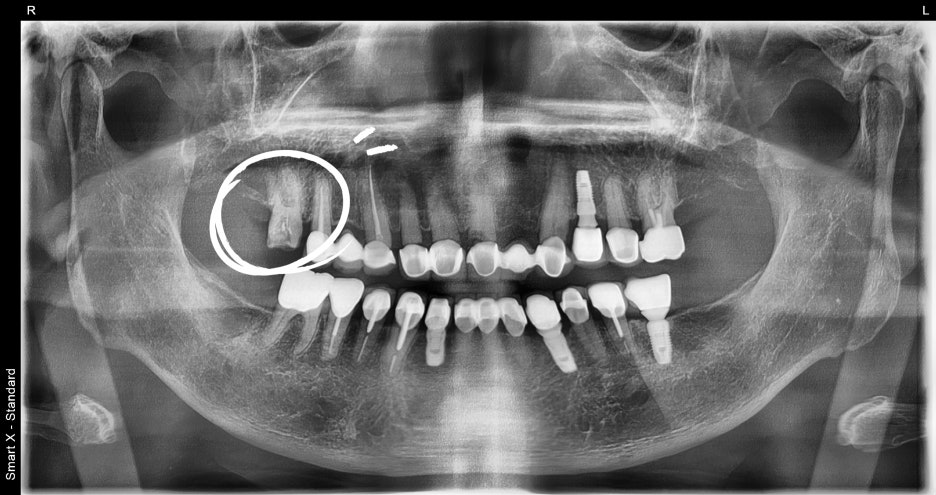

The patient had significant periodontitis and a buildup of tartar,

so we first performed panoramic imaging and tartar removal.

The examination results were as follows.

For a more precise assessment, an additional periapical X-ray was taken, and it was confirmed that the inflammation had spread all the way to the root tip of the tooth. At this stage, the root canal treatment plan was finalized.